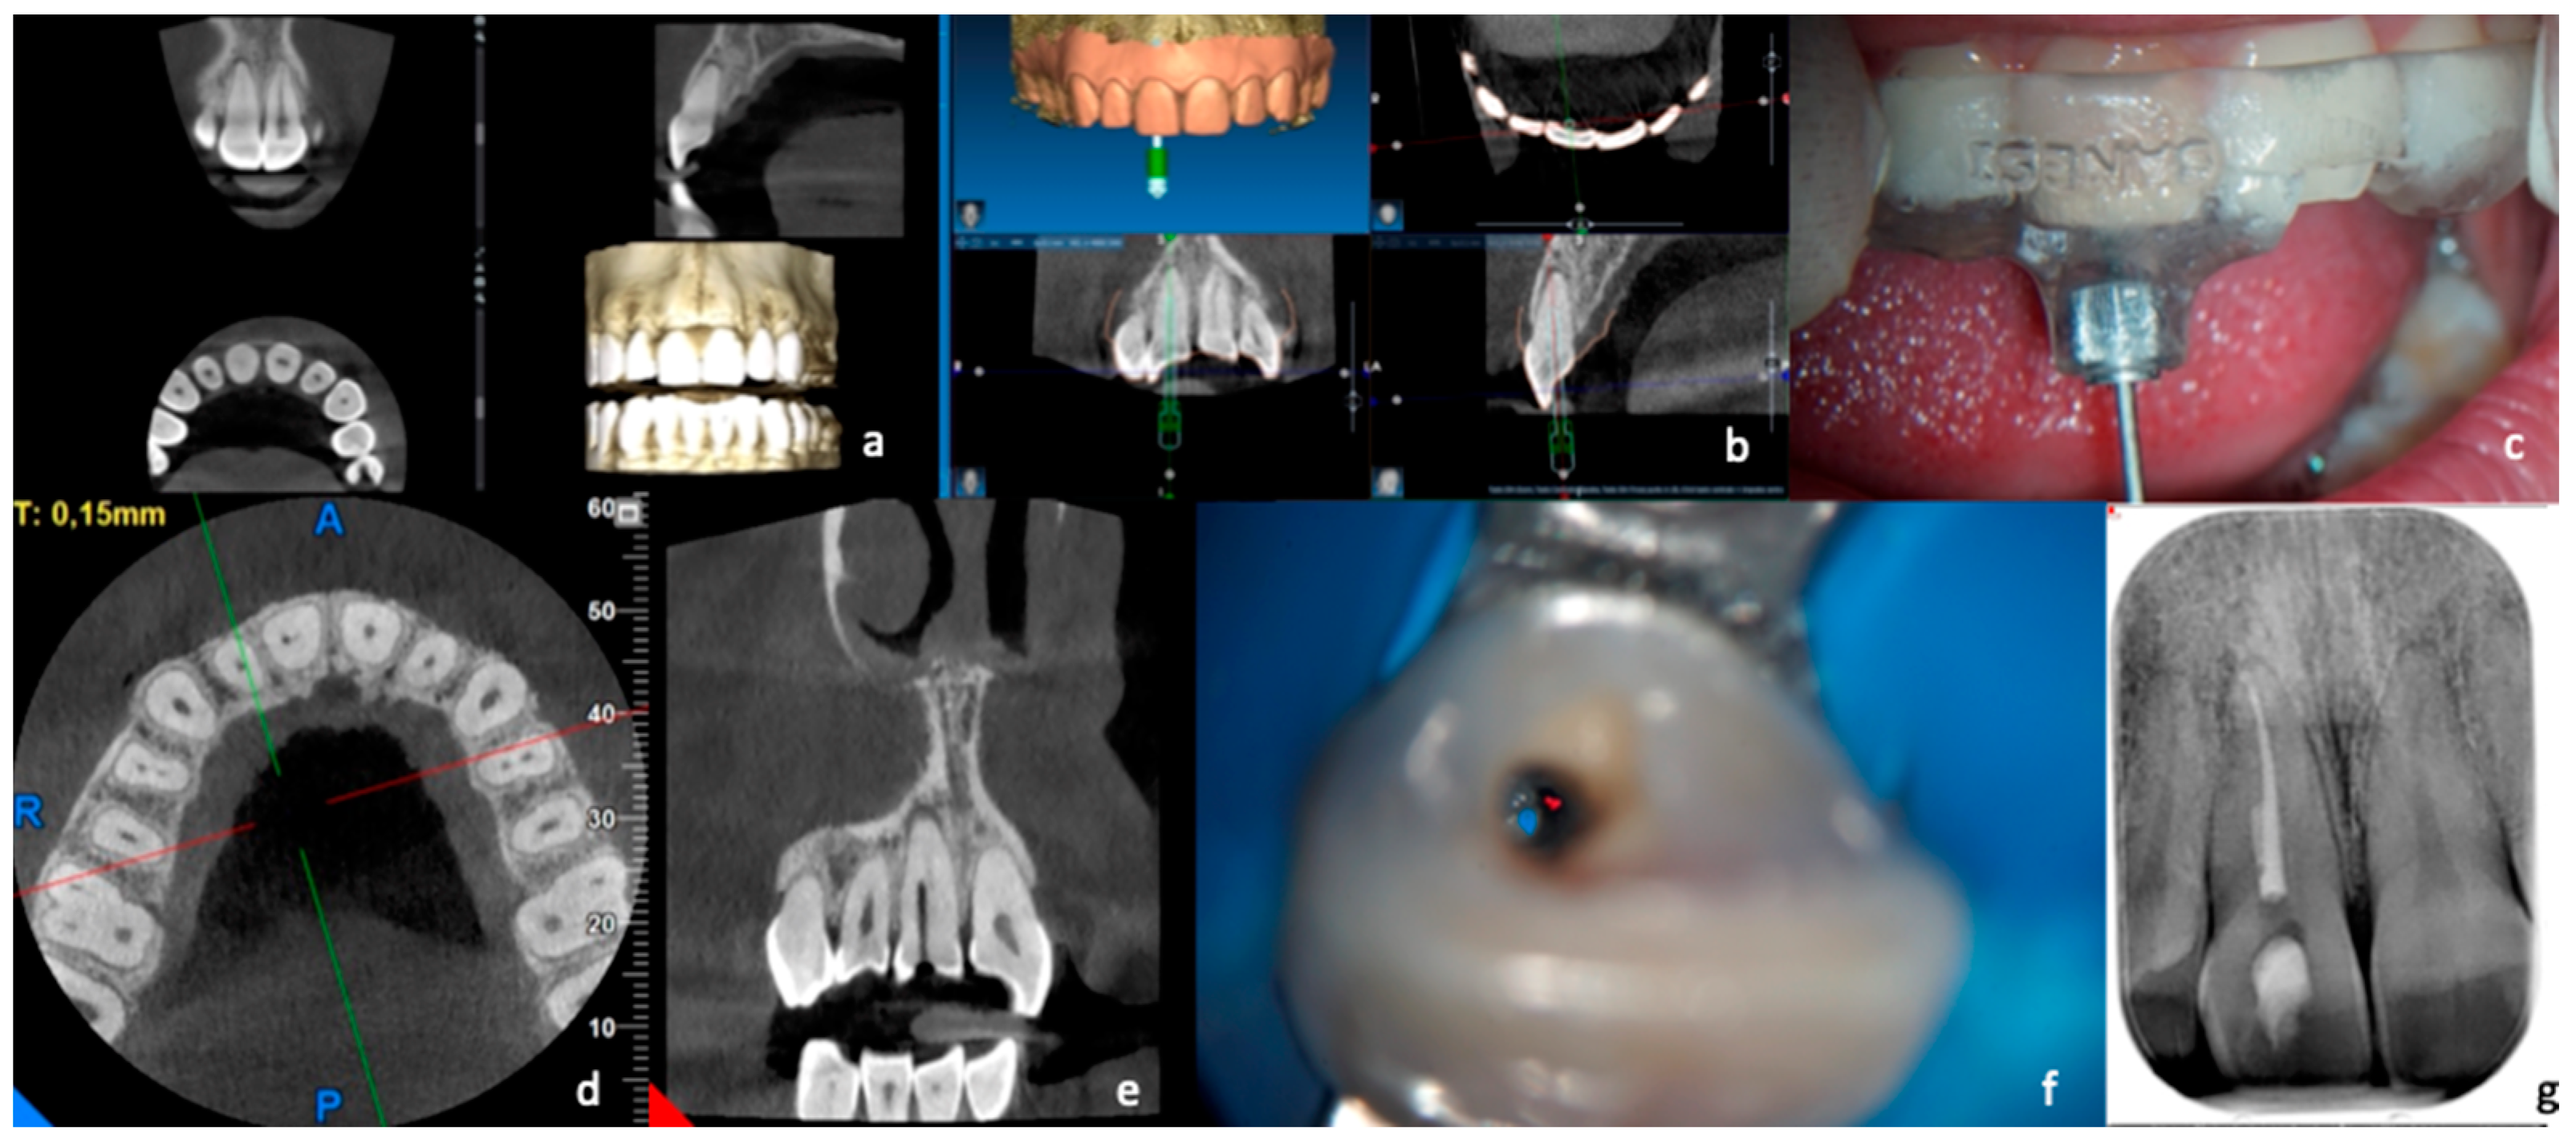

Figure 2. Treatment with “acceptable precision” of a calcified canal. The CBCT scan (a) and the optical impression were performed in this case. First, the data were processed to provide a virtual design of the guide (b), and then the artifact was created that was placed in position in the patient’s arch (c). Next, the drill was inserted up to the end of the “limit stop” and then, after several attempts, not finding the canal, a CBCT (d,e) was performed, which allowed highlighting of the position of the maximum penetration of the drill with respect to the patent canal. Finally, with the help of the microscope and ultrasound, the canal was found (f), shaped, and obturated (g).

For what regards those elements in which the canal was not immediately reached after the complete penetration of the bur (Figure 2), after several attempts made with the C+ steel instruments, two intraoral X-rays were carried out in different projections to locate the most apical point reached by the bur in relation to the beginning of the patent canal. In cases where it was impossible to reach the canal, a second CBCT examination according to a previous study [17] was carried out, with the same characteristics as the diagnostic one, requiring the patient to give written consent to this examination, as already stipulated in the first informed consent form.

The purpose was to understand where the tip of the bur ended up and the relationship of the patent channel with the point reached. For this purpose, the axial sections of the volumetric examination were primarily used. After the distance between the patent canal and the endpoint of the bur was recorded, the canal was widened using thin ultrasonic tips (ET 20-Satelec, Acteon, Merignac, France) in the direction of the point of canal patency under the control of the operating microscope (Pico-Zeiss, Oberkochen, Germany). Once access to the patent canal was detected, the endodontic treatment was carried out in the same way as indicated for the treatment of the canal with an optimal course.